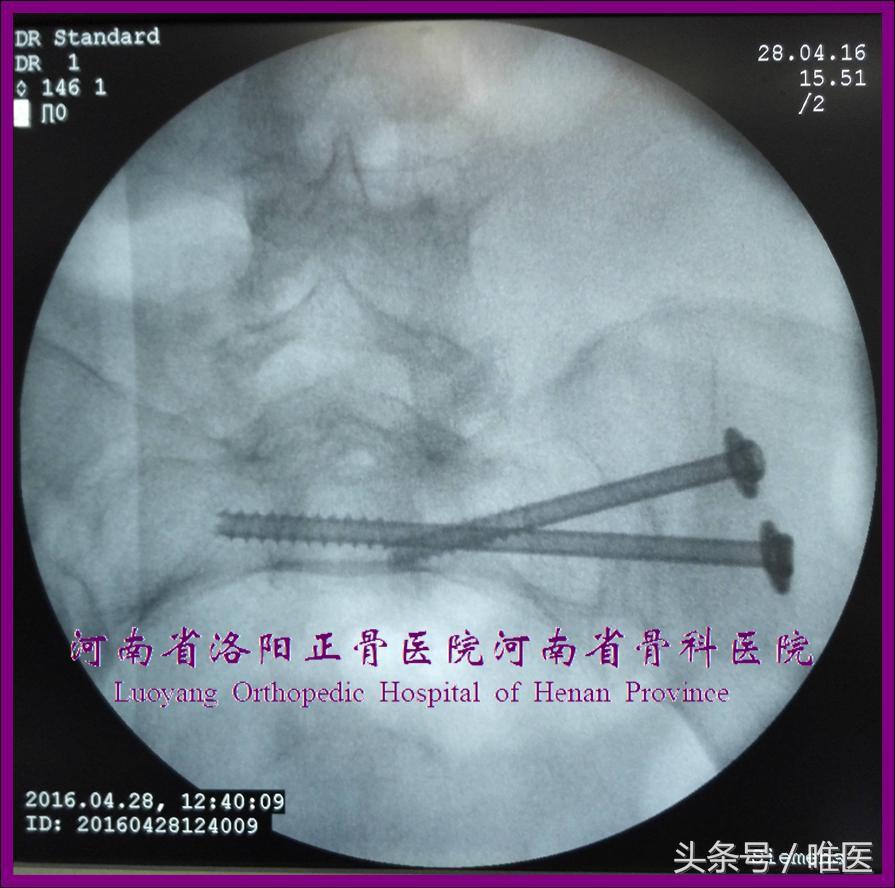

2. 骶2骶髂螺钉的置入技术

术前测量确定骶2节段是否存在安全置钉空间。如有安全空间,则按蔡鸿敏等所描述的置钉技术[22]进行置钉操作。(图13)

图13. 变异型上骶段骶2骶髂螺钉置入示例。